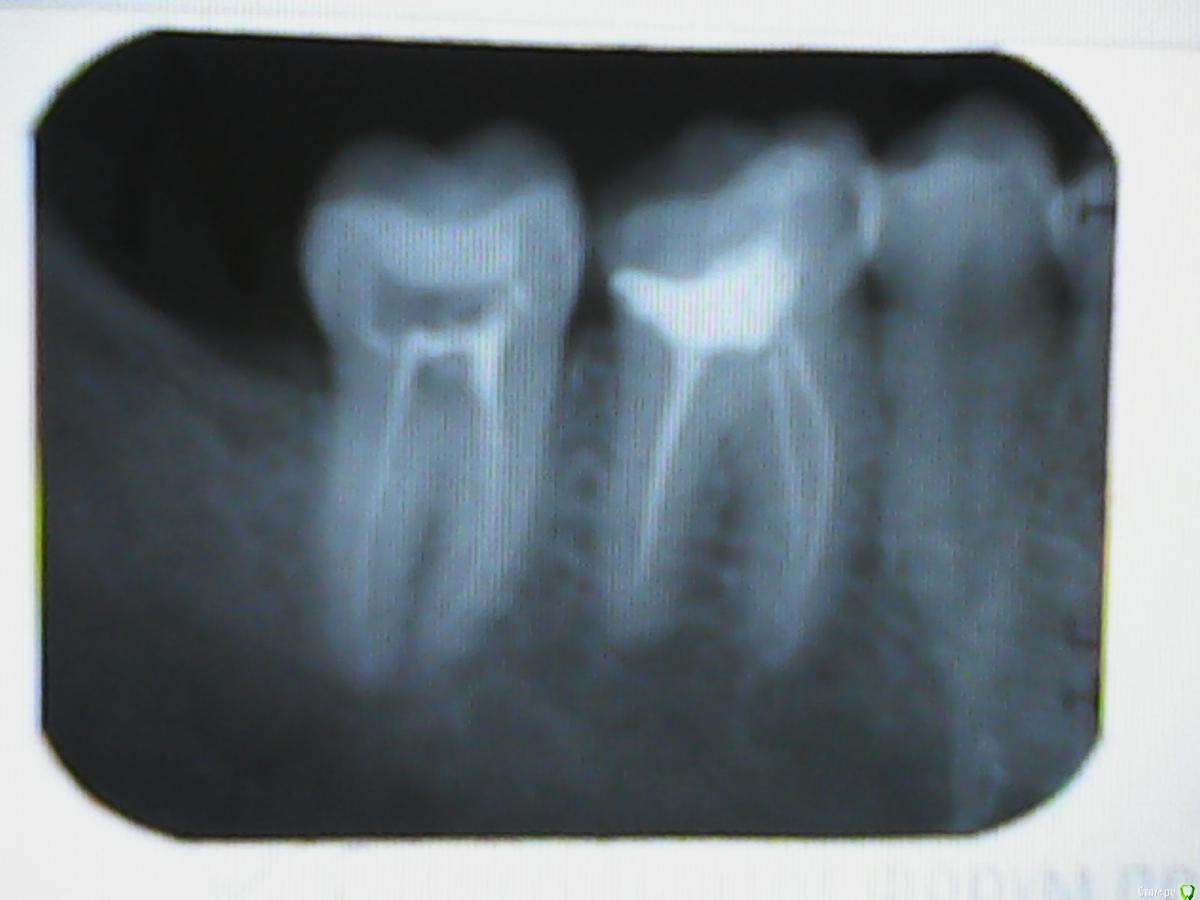

red_butler Опубликовано 27 ноября, 2016 Поделиться Опубликовано 27 ноября, 2016 если этот снимок контрольный, то седьмой зуб нужно перелечивать Ссылка на комментарий

zdoroviy Опубликовано 27 ноября, 2016 Автор Поделиться Опубликовано 27 ноября, 2016 если этот снимок контрольный, то седьмой зуб нужно перелечиватьда контрольный, сделали неделю назад. А что конкретно перелечивать что бы я мог сказать доктору? Плохо запломбированы каналы? Ссылка на комментарий

red_butler Опубликовано 27 ноября, 2016 Поделиться Опубликовано 27 ноября, 2016 А что конкретно перелечивать что бы я мог сказать доктору? Доктору ничего говорить не надо, не благодарное это дело. Ищите грамотного эндодонтиста и перелечивайте зуб. 2 Ссылка на комментарий